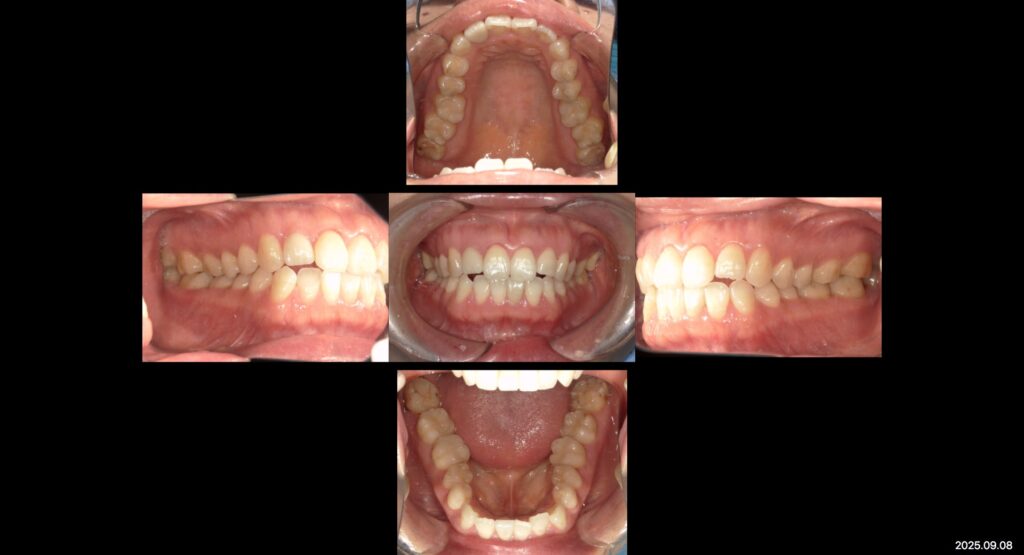

下:治療後口腔内写真

見た目と噛み合わせ改善を目的に銀をセラミックの補綴物に替える根本治療を行いました。

見た目もメタルフリーになり目立つ所なく噛み合わせもしっかり合い理想的な噛み合わせとなり

現在はメンテナンスに通っていただきながら経過観察を追っております。